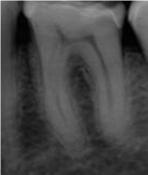

Antes![]() |